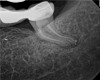

As indicated in Figure 11, the mesial aspect of the distal canal was never touched by instruments, yet he was able to clean, evidenced by the postoperative image. In the past, a case with this level of difficulty would have required at least two appointments, with an interim medication of calcium hydroxide, but the case was treated in a single-visit appointment.  As observed 7 months later (Figure 12), the patient returned completely asymptomatic, and complete bone healing had occurred that exceeded initial expectations.

Fig 11. Case 2: Significant bone loss on the mesial and apical aspect suggested a potential vertical fracture (Fig 9 and Fig 10). Radiographic images were taken immediately postoperatively (Fig 11) and 7 months postoperatively (Fig 12).

Figure 11